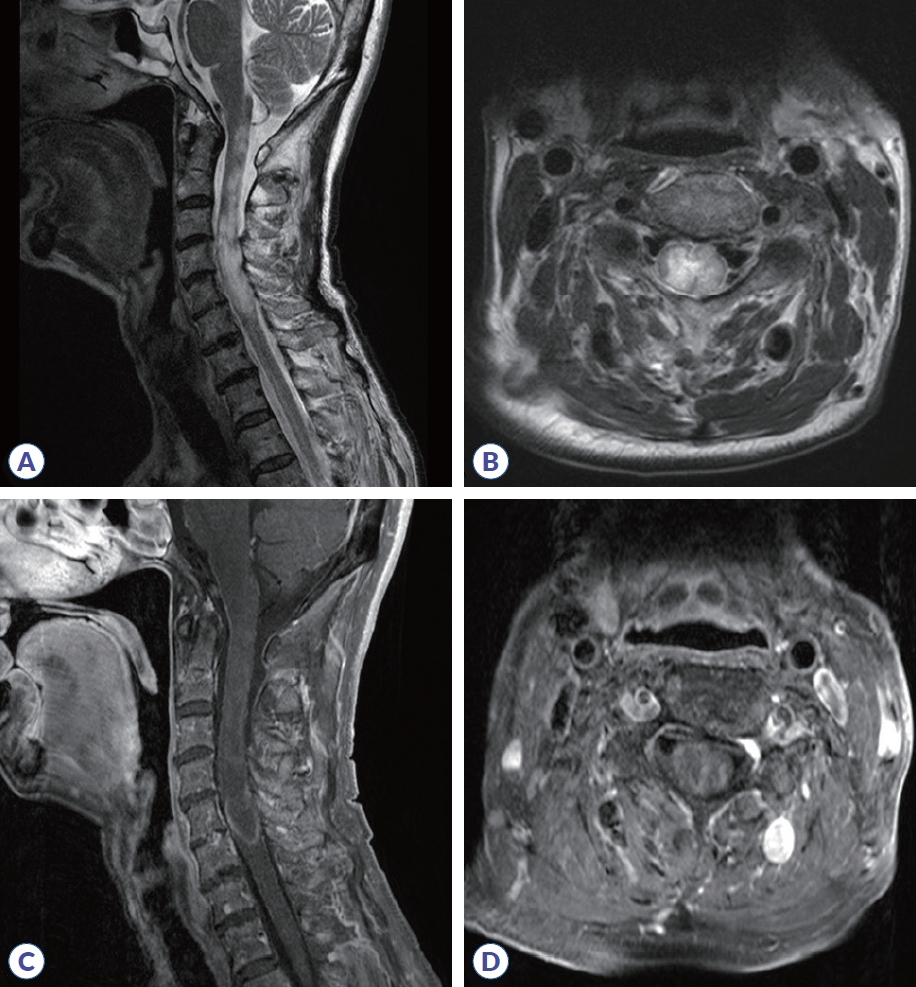

Figure 1.

Cervical spinal MRI. (A) Sagittal T2-weighted imaging shows diffuse cord swelling and hyperintensity extending from the cervicomedullary junction to the C6 level. (B) Axial T2-weighted imaging of the upper cervical level shows bilateral hyperintensity, more pronounced on the right. (C) Sagittal post-contrast T1-weighted imaging reveals patchy intramedullary enhancement in the cervical cord. (D) Axial post-contrast T1-weighted imaging shows inhomogeneous enhancement at the mid-cervical level. MRI, magnetic resonance imaging.